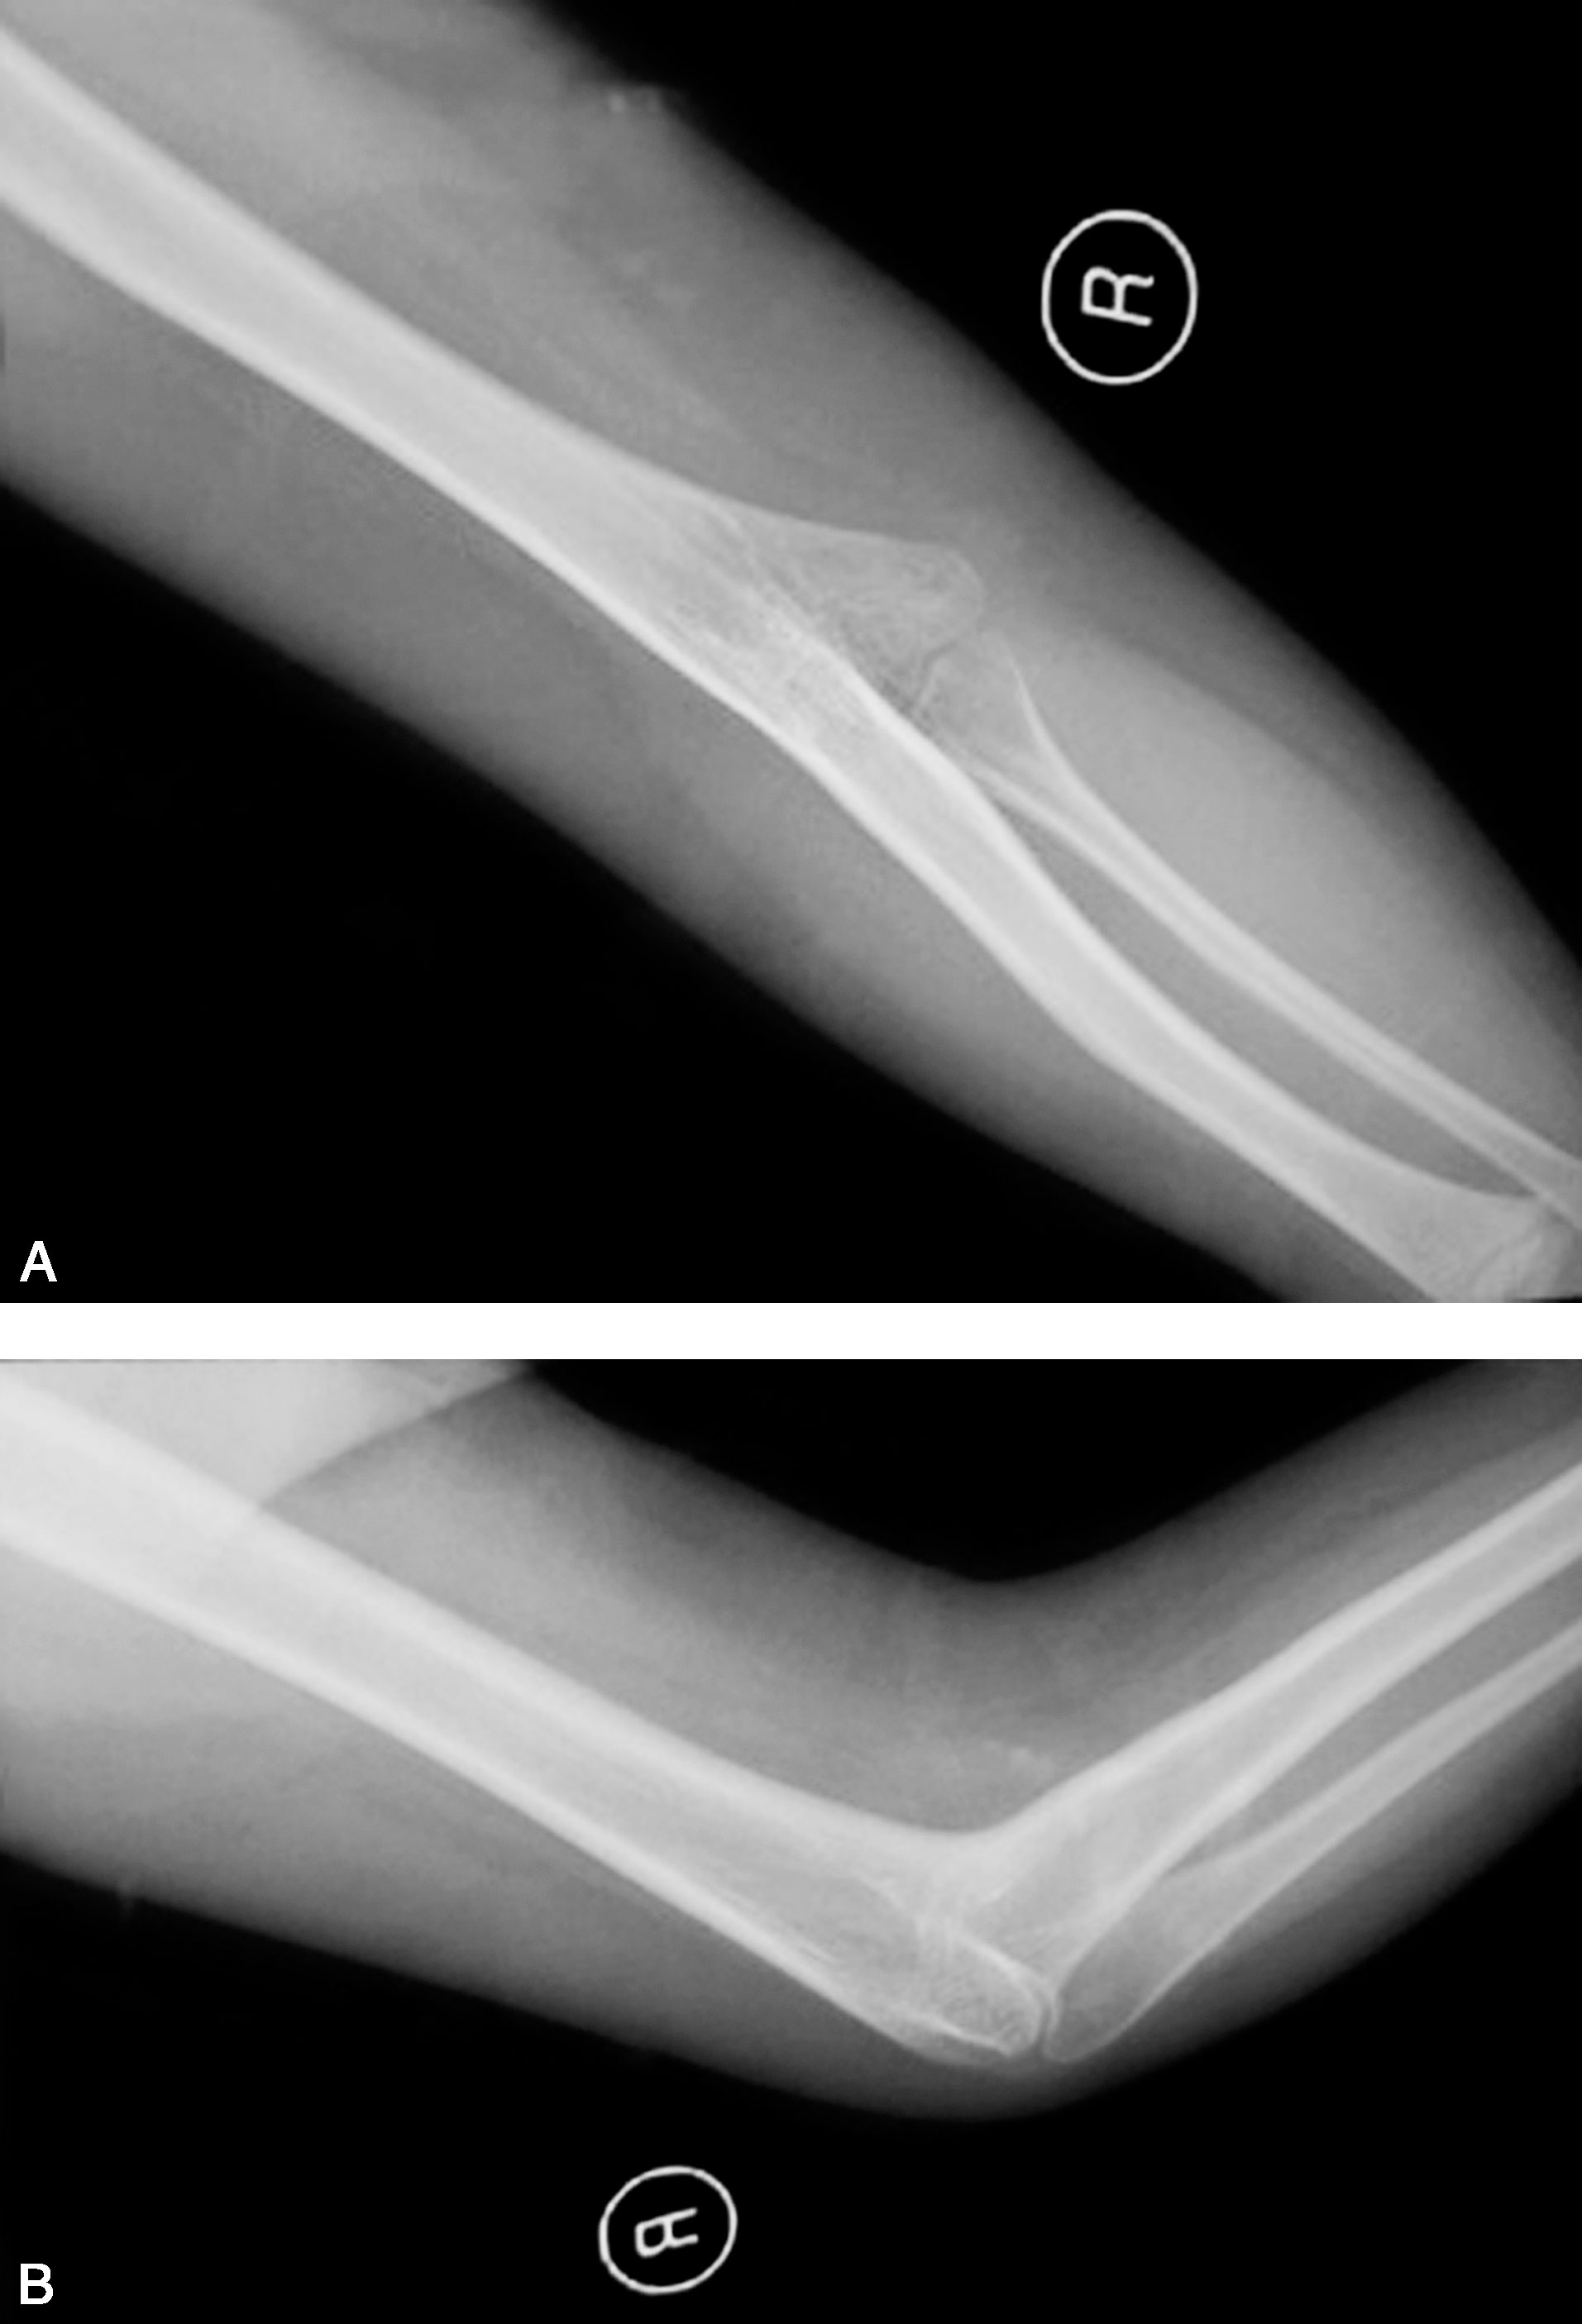

图1-2-20 肱骨桡骨骨性融合病例

X 线正位片(A)和侧位片(B)显示右侧前臂肱桡骨骨性融合,合并尺骨发育不良